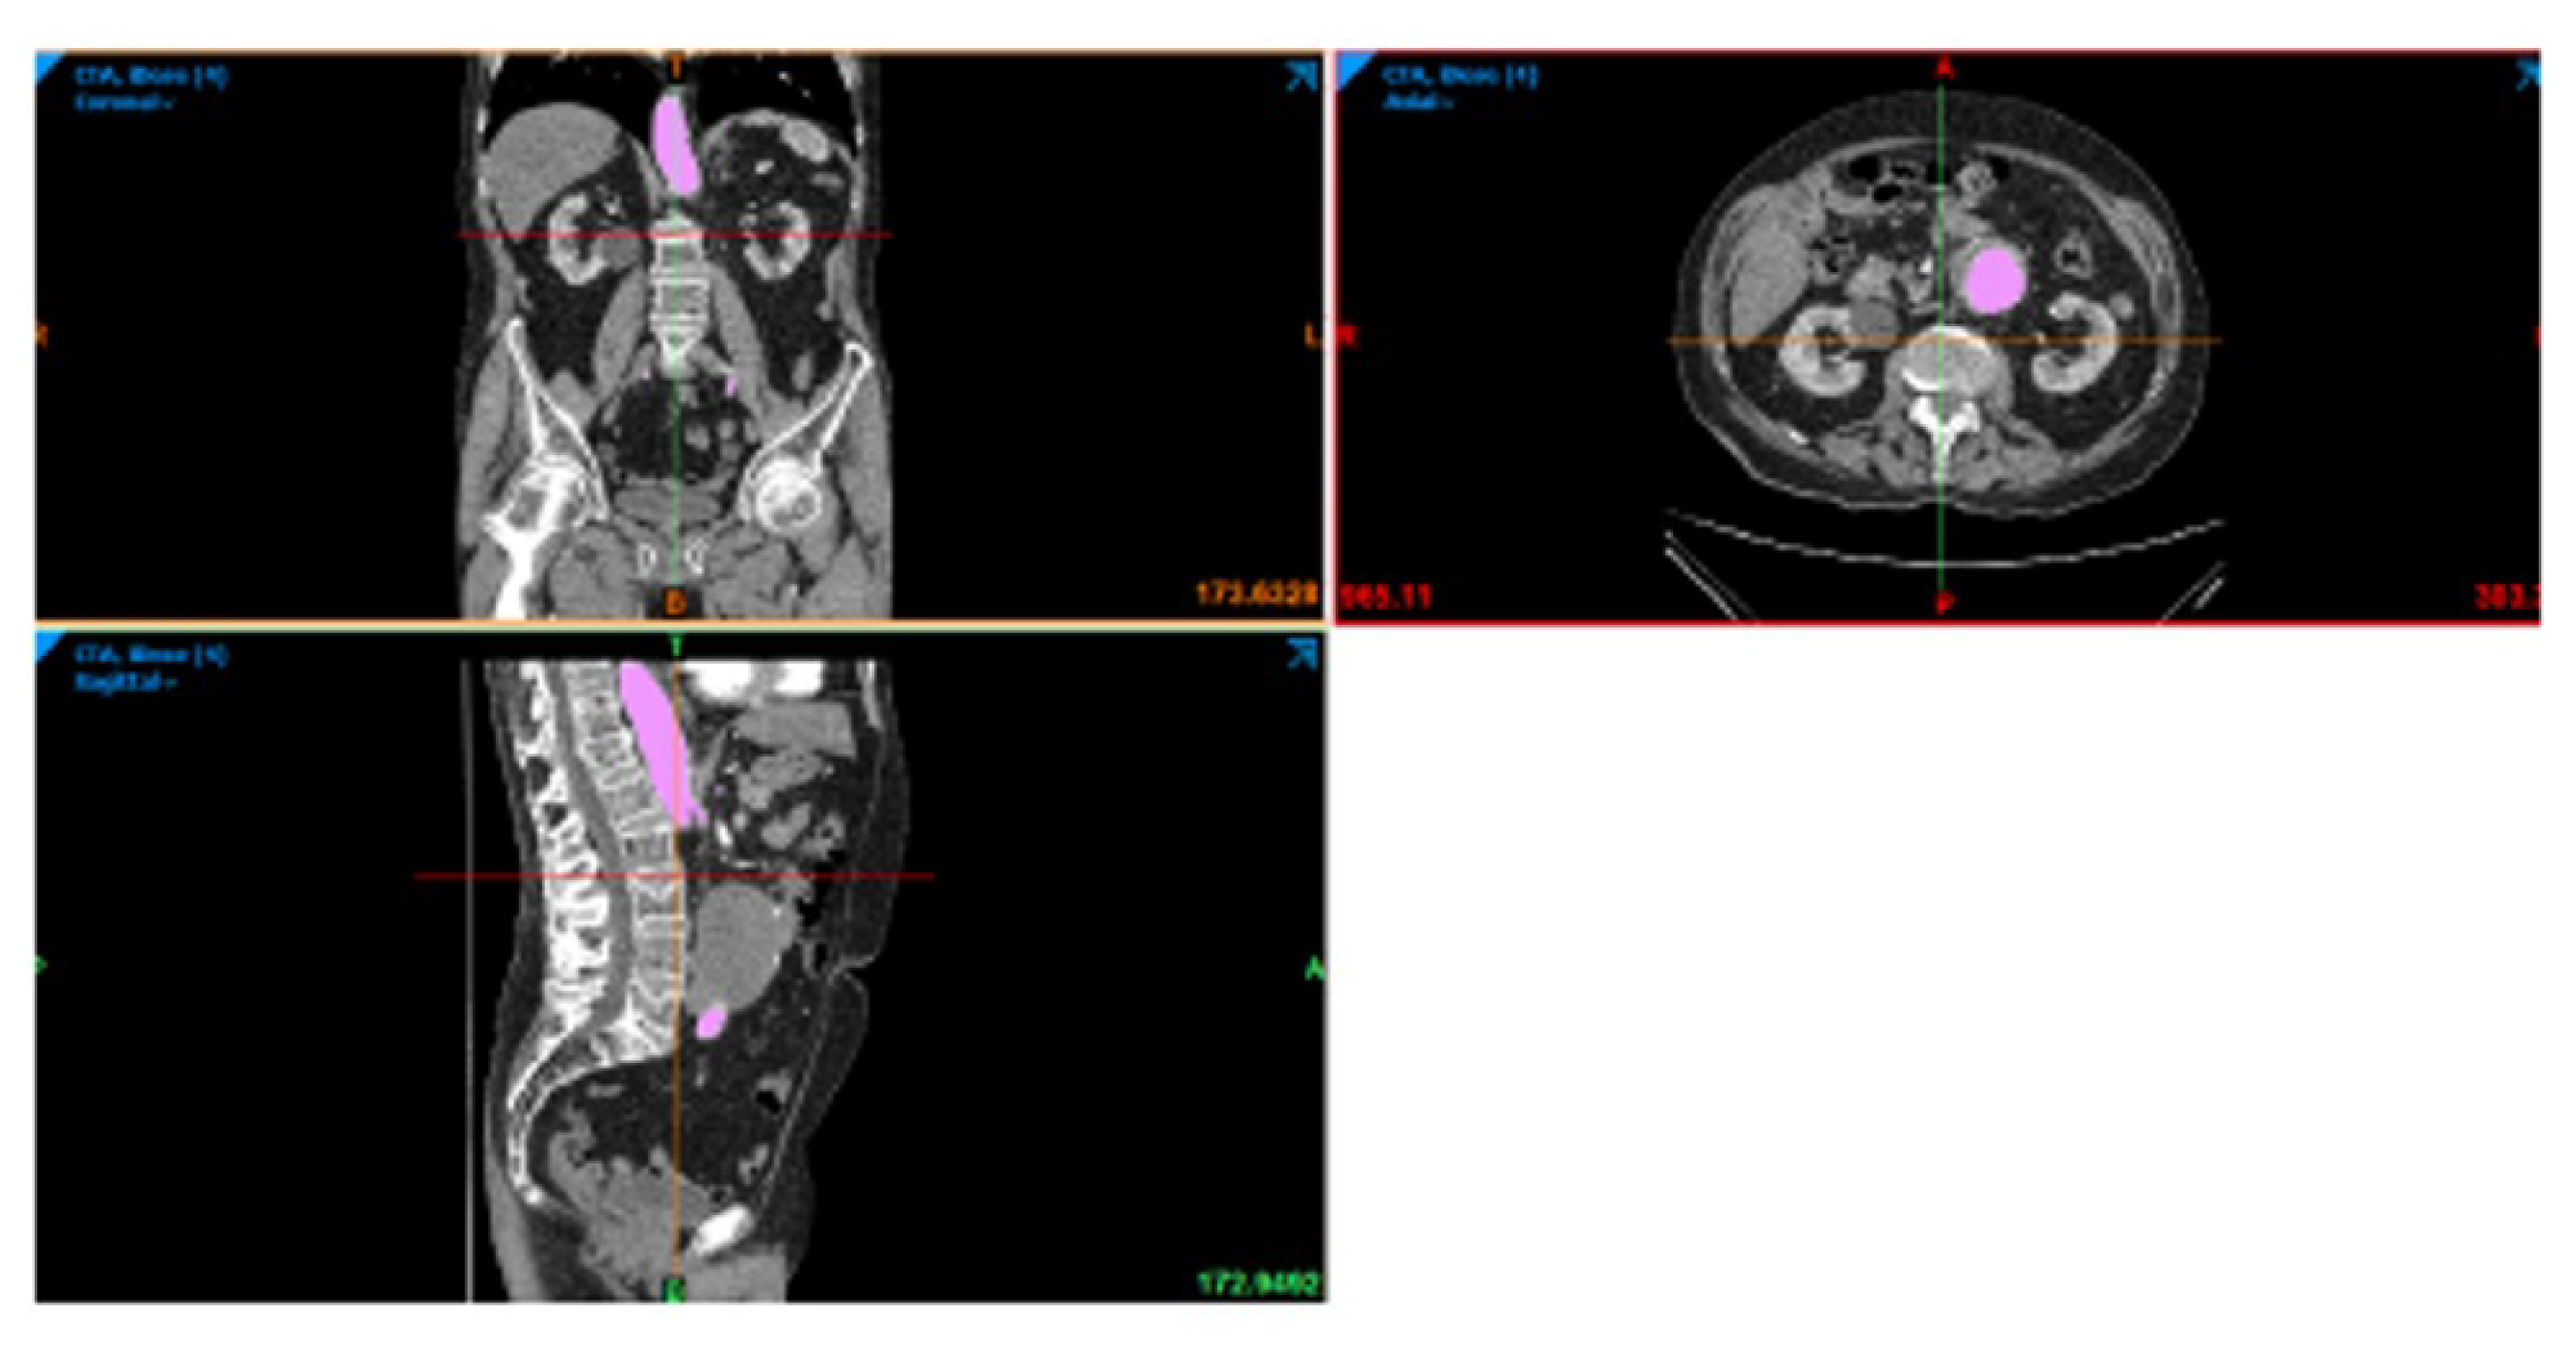

2. Materials and Methods